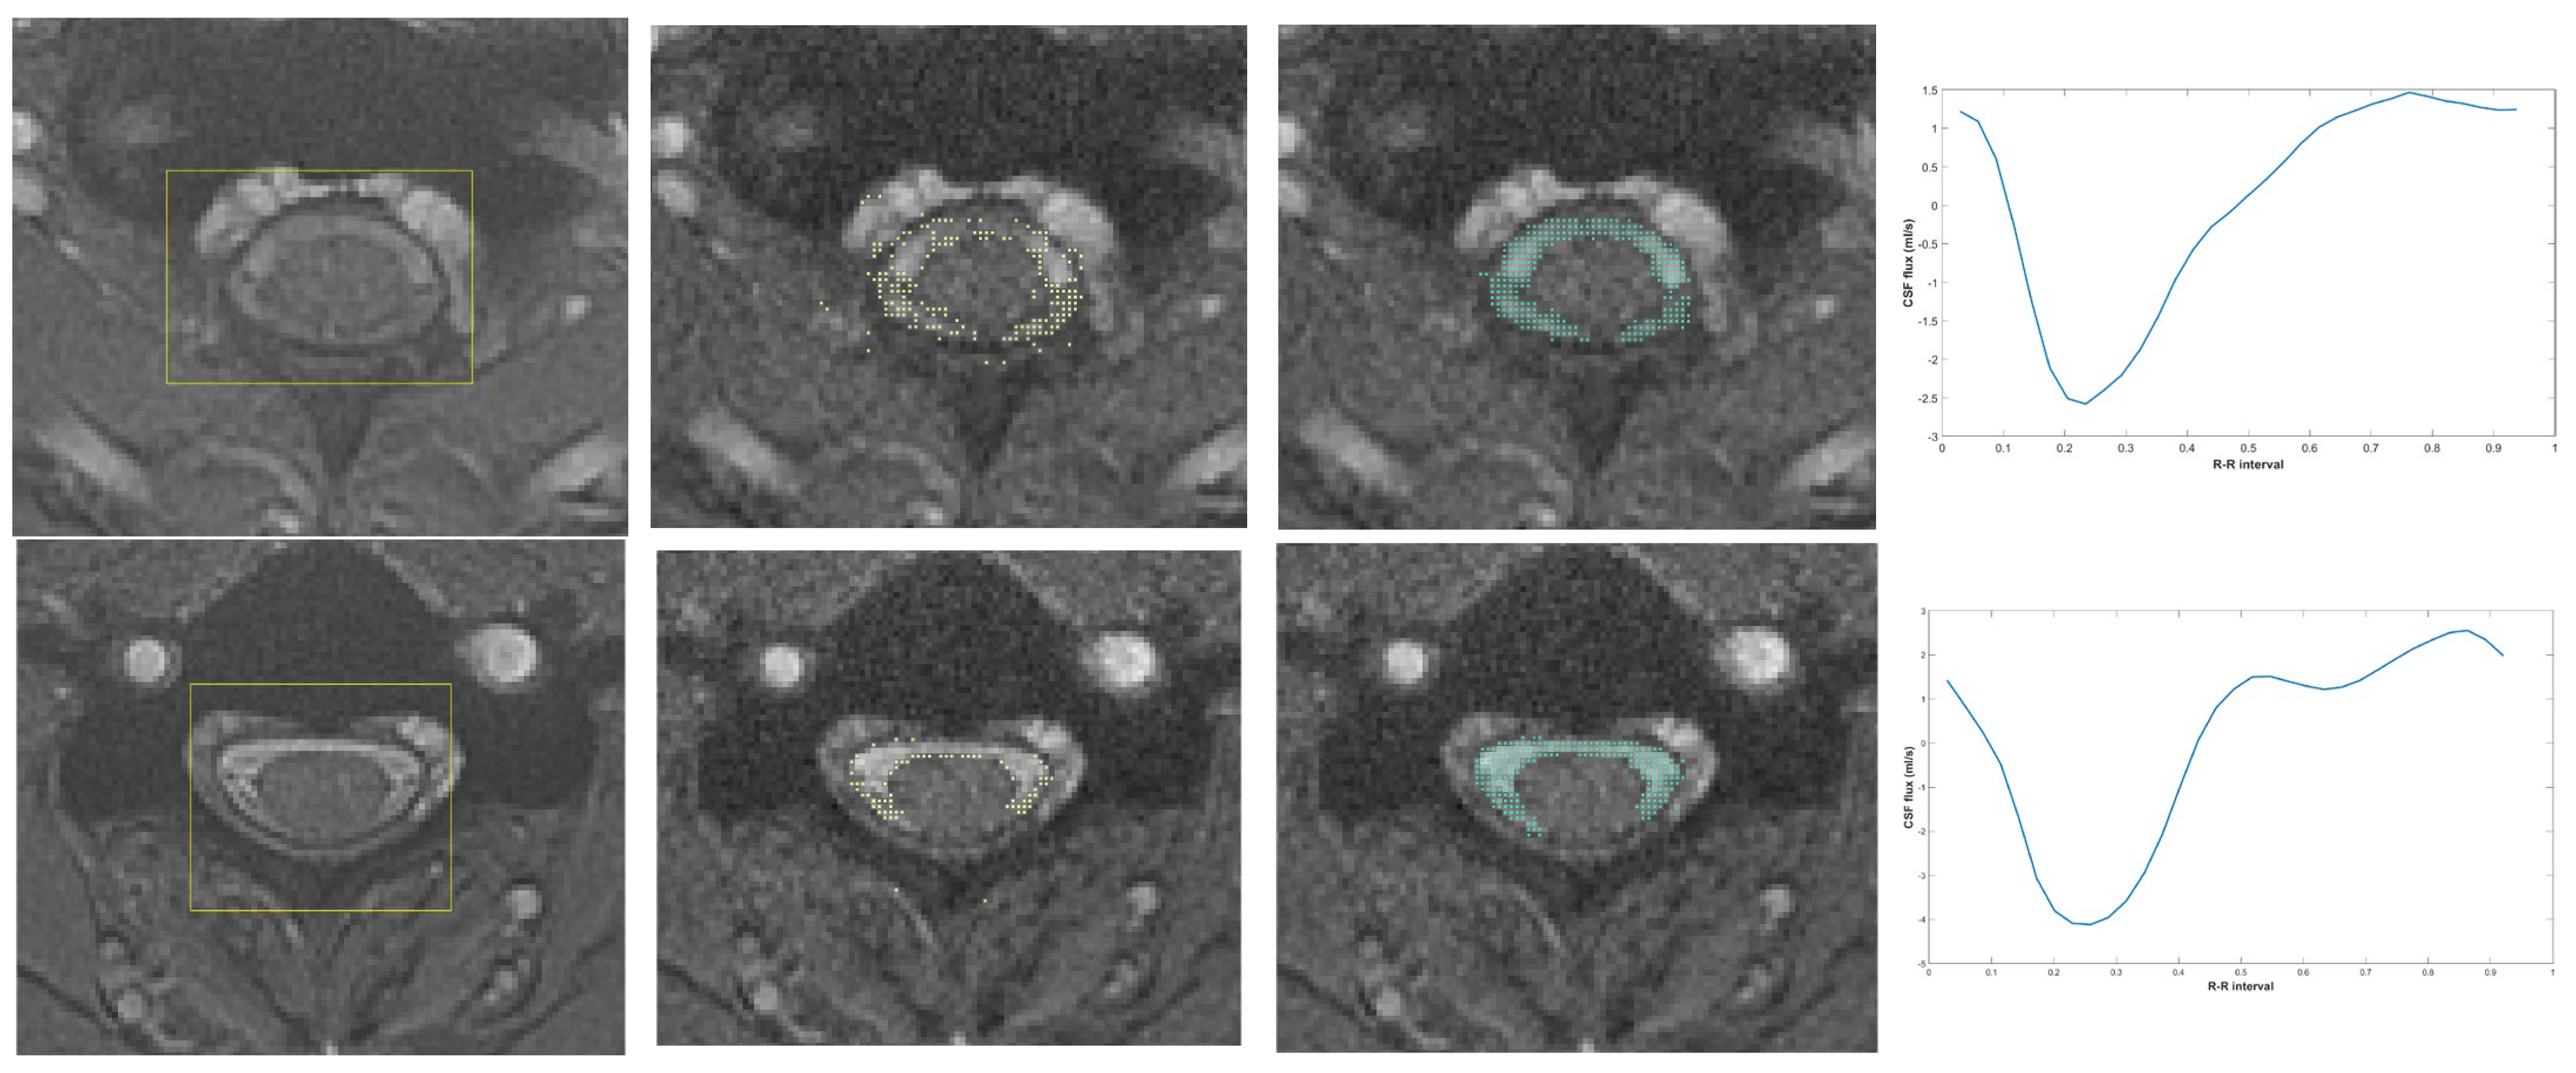

2.3. Artificial Intelligence-Based Flow Analysis

CSF Region Detection

- Fu, J.; Chai, J.W.; Chen, P.L.; Ding, Y.W.; Chen, H.C. Quantitative Measurement of Spinal Cerebrospinal Fluid by Cascade Artificial Intelligence Models in Patients with Spontaneous Intracranial Hypotension. Biomedicines 2022, 10, 2049. [Google Scholar] [CrossRef]

- Tsou, C.-H.; Cheng, Y.-C.; Huang, C.-Y.; Chen, J.-H.; Chen, W.-H.; Chai, J.-W.; Chen, C.C.-C. Using deep learning convolutional neural networks to automatically perform cerebral aqueduct CSF flow analysis. J. Clin. Neurosci. 2021, 90, 60–67. [Google Scholar] [CrossRef] [PubMed]

- Alperin, N.; Lee, S.H. PUBS: Pulsatility-based segmentation of lumens conducting non-steady flow. Magn. Reson. Med. 2003, 49, 934–944. [Google Scholar] [CrossRef]